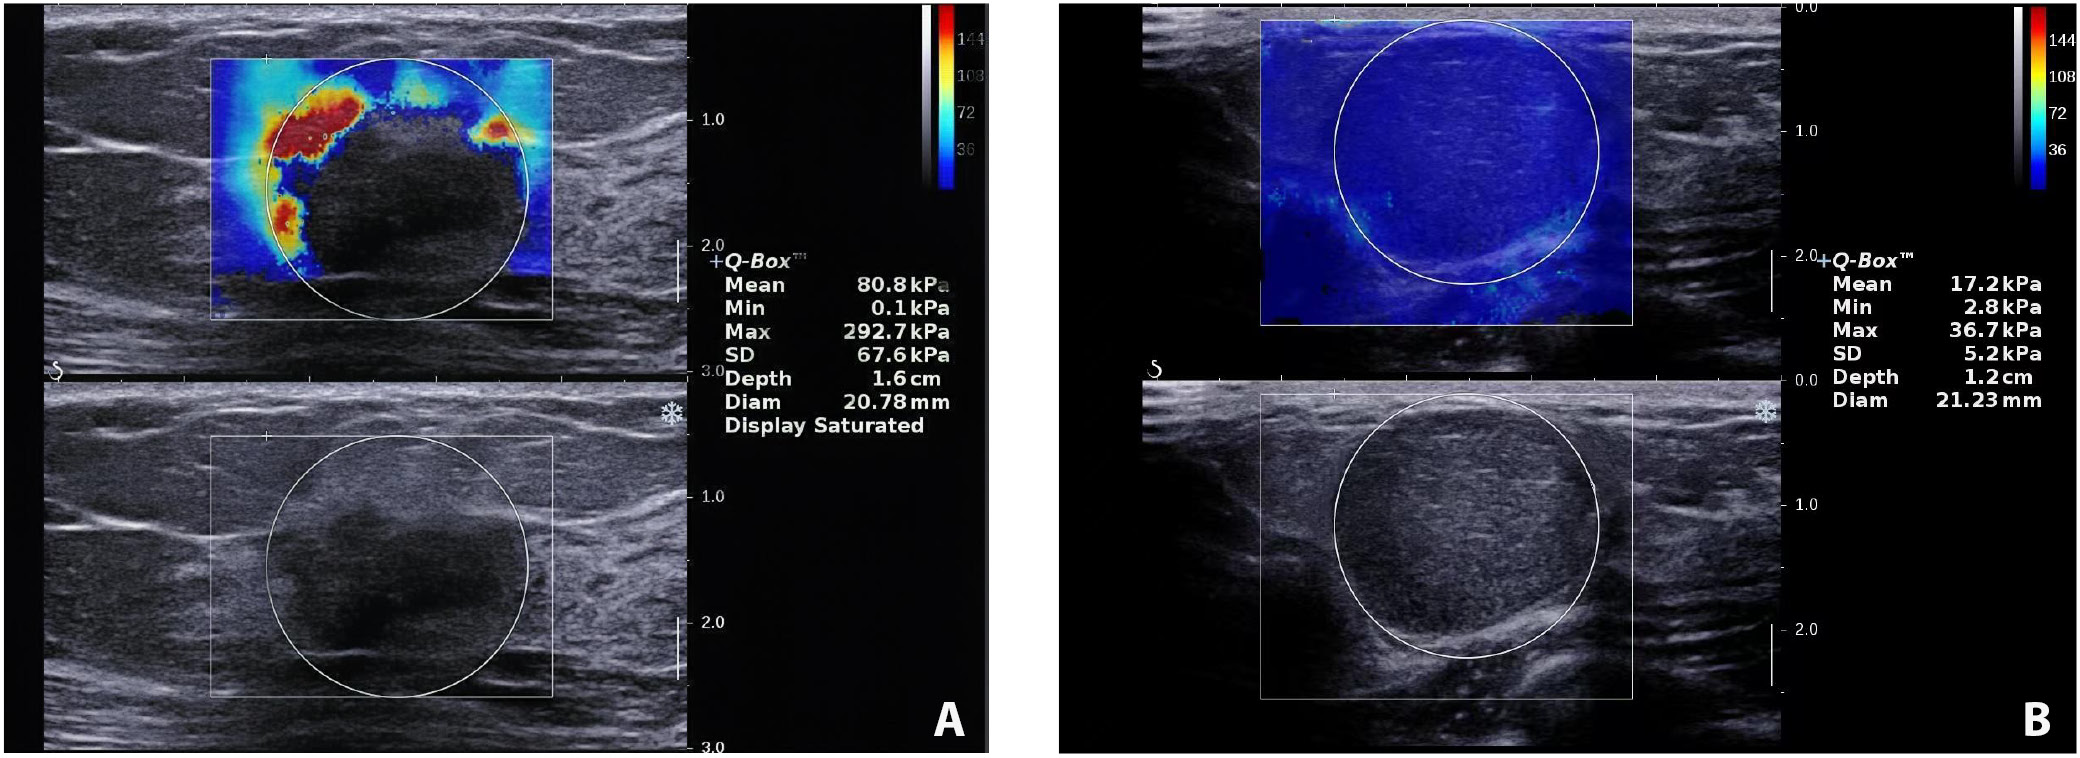

Shear-wave elastography evaluation of breast lesions

Table 2 summarizes the 4 SWE parameters measured. The malignant group demonstrated higher E-max (151.96 kPa vs 69.65 kPa; t(97) = −9.66, p < 0.001), E-mean (92.30 ±13.05 vs 30.04 ±9.28; t(53) = −24.97, p < 0.001), E-sd (13.09 ±2.45 vs 8.98 ±2.47; t(97) = −7.93, p < 0.001), and E-ratio (14.77 ±3.50 vs 3.39 ±0.80; t(35) = −18.99, p < 0.001) compared to the benign group (Table 2). Representative SWE images from the malignant and benign groups are presented in Figure 1.

The SWE evaluation in our cohorts demonstrated that the elastic parameters (E-max, E-mean, E-sd, and E-ratio) in the malignant lesions were all significantly higher than those in benign diseases. Our results are consistent with the findings by Schaefer et al. that significantly higher elasticity in malignant lesions was observed.11 Though the exact mechanism of the “stiffness” of malignant lesions is unknown, several possibilities have been proposed. Wang’s team evaluated the extracellular matrix (ECM) components in benign and malignant breast lesions and found a higher concentration of collagen and elastic fibers in the ECM of cancerous tissues. These findings suggest that alterations in ECM composition may contribute to the increased stiffness observed on ultrasound elastography.35 Xue et al. conducted a more in-depth molecular investigation and found that hypoxia-inducible factor 1-alpha (HIF-1α), in conjunction with Kindlin-2, plays a role in promoting collagen formation in breast cancer tissues.36, 37 Other possible mechanism might involve more intense immune response around cancer cells or rapid growth of cancer cells, which all remains to be proven by more research.